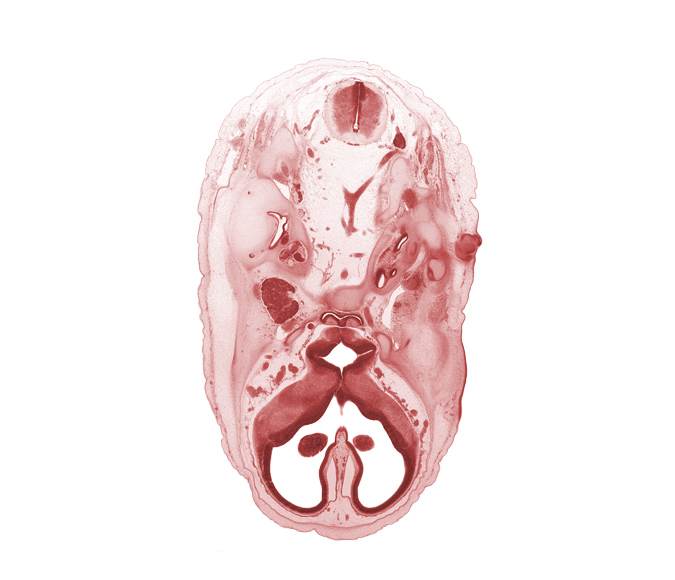

Carnegie Embryo #462 | Location: 5-04-03

Keywords: C-1 spinal ganglion, abducens nerve (CN VI), adenohypophysis, anterior cerebral artery, artifact separation(s), basi-occipital (basal plate), basilar artery, central canal, cerebral vesicle (telencephalon), dorsal funiculus, facial nerve (CN VII), hypoglossal nerve (CN XII), interventricular foramen, junction of vertebral arteries, lateral funiculus, lateral ventricle, mandibular nerve (CN V₃), maxillary nerve (CN V₂), medial ventricular eminence (diencephalon), ophthalmic nerve (CN V₁), optic canal, orbitosphenoid, spinal accessory nerve (CN XI), third ventricle, tip of cochlear duct, vagus nerve (CN X), ventral funiculus, vertebral artery

Source: The Virtual Human Embryo.